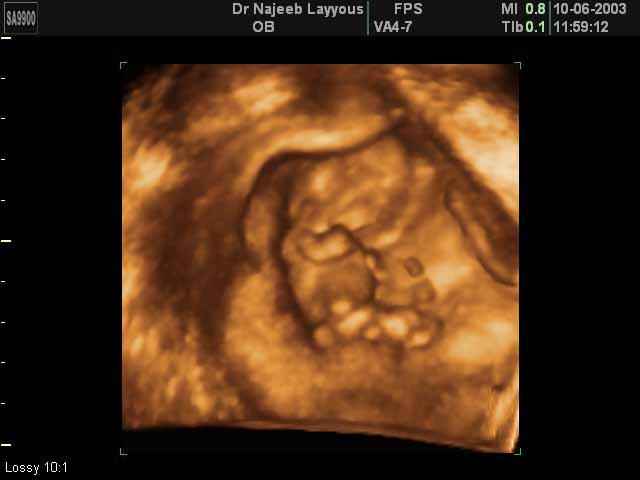

3D First Trimester Ultrasound Scan Photos